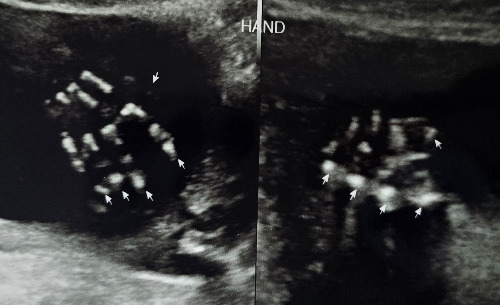

매주 산부인과를 찾을 때마다 베일을 벗기듯 둥글이에 대해서 하나씩 알아갈 수 있었다. 손가락, 발가락 개수가 10개라는, 살아가면서 당연하게 여겼던 사실조차 태아에게는 계단처럼 딛고 올라야 할 미션이었다.

12주 차가 되면서 태아의 다운증후군 여부를 판단할 수 있는 투명대 검사를 했다. 의사 선생님이 초음파 화면을 유심히 들여보는 동안의 초조함은 지금도 잊을 수 없다.

1-8.jpg

1-9.jpg

코, 입, 손가락 10개... 누구나 당연히 생각하는 것이지만 아이에게는 하나하나가 고비다.

임신 중반을 지나면서 아내의 배가 점점 불러왔다. 여전히 입덧이 있었지만 초기보다는 많이 나아져서 먹을 수 있는 음식도 많이 늘어났다. 계속 줄어들기만 하던 몸무게도 양수와 둥글이의 영향인지 다시 늘기 시작했다. 27주 차에 두 번째 입체초음파 검사를 하였다. 입체 초음파 검사는 일반 초음파와 달리 아이의 형상을 3D 입체 영상으로 확인할 수 있는 검사다. 이미 12주 차 첫 번째 입체초음파 검사를 했었는데, 이때는 둥글이의 머리통과 팔다리 형상만 겨우 구분할 수 있었다. 그런데 두 번째 입체초음파 검사는 달랐다. 우리 부부는 이날 둥글이의 얼굴을 처음으로 선명하게 보았다.

1-10.jpg

1-11.jpg

12주 차와 27주 차의 입체 초음파 사진. 한 화면에 들어오지 않을 만큼 컸다.

어느새 쑥쑥 자라 한 화면에 담을 수도 없는 둥글이는 슬며시 얼굴 반쪽을 내보여 주었다. 감고 있는 눈과 작은 코, 심통 난 듯 불퉁한 볼과 입까지... 마치 아이를 눈앞에 두고 있는 듯 생생한 모습이었다.